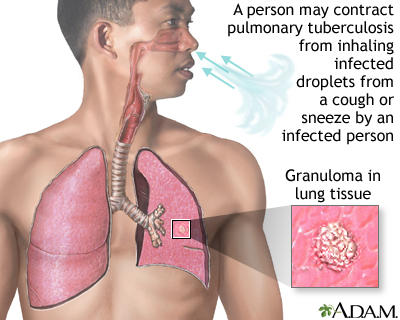

Many other vaccines are available, including vaccines for:

- Tuberculosis

These vaccines are not routinely given to the general population. They are only recommended to people who are at risk of exposure to the specific germ. For more information about these vaccines, visit the CDC website -- www.cdc.gov/vaccines/vpd/vaccines-diseases.html.